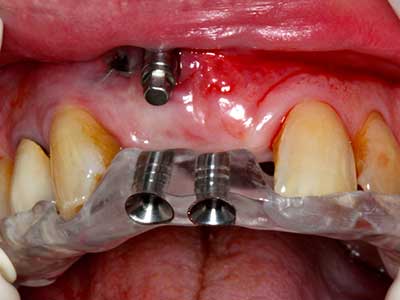

Bone tissue is not simply a mineral structure but also contains a substantial proportion of collagen fibres. This means it not only has good compressive strength but also a degree of flexibility, which can be taken advantage of when performing bone augmentations. In the classical expansion procedure using bone splitting, the atrophied alveolar ridge is split longitudinally and carefully expanded after reaching an adequate osteotomy depth (Fig. 13-16), ideally without substantial removal of the periosteum (Brugnami, Caiazzo et al. 2014, Stricker, Fleiner et al. 2014). Screw and plate systems with increasing expansion distance have proven effective in separating the two bone lamellae while remaining below the fracture threshold. In general, residual bone widths of at least 3–4 mm are required (Chiapasco, Zaniboni et al. 2006) to guarantee adequate flexibility and sufficient bone coverage of the future implants. If necessary, a vertical relief osteotomy on one or both sides can improve flexibility. A combination with additional augmentation techniques, particularly on the buccal side, has been described as an alternative to the classical technique.

The splitting procedure is particularly atraumatic and there is no significant loss of dimension when using piezosaws, and there are no significant differences between implants in split jaws and implants in an alveolar ridge without a bone deficit (Chiapasco, Zaniboni et al. 2006, Danza, Guidi et al. 2009). However, sufficient continuous irrigation is essential, particularly with locally restricted and deep splitting to prevent thermal stress in the apical osteotomy regions.